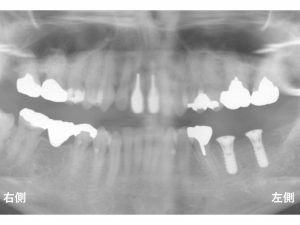

以下が治療前です。

下顎左側の奥歯が2歯欠損されている患者様です。

以下は、

インプラントを埋め込む治療を行った直後です。

この後、

インプラントと骨がしっかりとくっつく(結合する)まで

約2〜3ヶ月待ちます。

以下は、型を取り、被せ物を装着して、

治療が終了した状態です。

これで、

左右の奥歯でしっかりと噛むことができます。